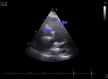

The diagnosis of atrial septal defect (ASD) may be delayed until adulthood or even later in life as it is a well-tolerated congenital heart disease. If patients are not examined and investigated well in childhood, the diagnosis may be delayed until later in adulthood when patients present with palpitations and sometimes dyspnea due to the right chambers dilatation from right ventricular volume overload. In this report, we present a case of a 50-year-old female patient with symptoms of heart failure and atrial fibrillation who was found to have dilated right cardiac chambers, dilated pulmonary artery, severe tricuspid regurgitation, pulmonary hypertension, and a pulmonary-to-systemic flow ratio (Qp/Qs) of more than 1.5 by transthoracic echocardiography and Doppler, indicating left to right shunt at the atrial level. However, transthoracic echocardiography could not visualize the defect, and two-dimensional (2D) transesophageal echocardiography was done in this patient and documented the presence of a sinus venosus ASD with an incomplete cor triatriatum dexter membrane; all four pulmonary veins were identified going to the left atrium. Since the presence of an incomplete cor triatriatum dexter membrane (despite causing no symptoms) makes the percutaneous closure of the sinus venosus ASD and the percutaneous repair of tricuspid regurgitation very difficult, we decided to advise surgical ASD closure and tricuspid valve repair for the patient.